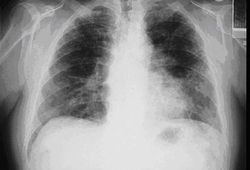

Asbestosis

Posterior-anterior view of the chest with bibasilar linear interstitial changes consistent with asbestosis

From the personal collection of Kenneth D. Rosenman MD